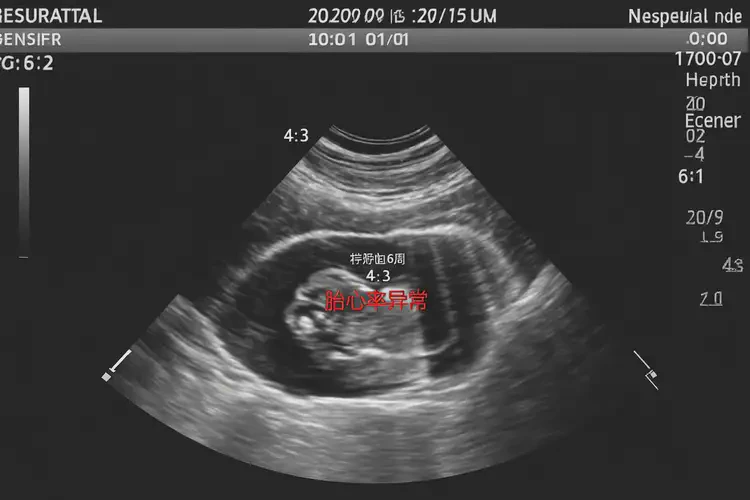

懷孕第6周胎心率72還能保住嗎

胎心率72次/分鐘在懷孕第6周可能存在風險

懷孕第6周胎心率72次/分鐘低于正常范圍,通常正常胎心率在120-160次/分鐘之間。胎心率受多種因素影響,包括胎兒發(fā)育階段、孕婦健康狀況等,因此不能僅憑一次測量結(jié)果判斷胎兒是否能保住。

懷孕第6周胎心率72還能保住嗎(圖1)